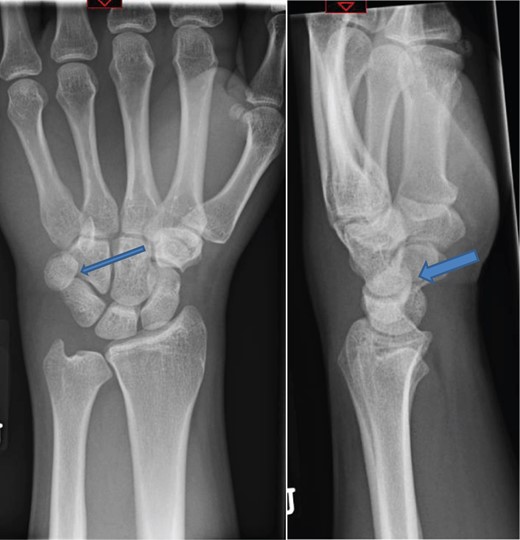

The patient was taken to theatre the following day where a closed reduction of the dislocated pisiform was attempted, however it was unsuccessful. Therefore we then proceed to an open reduction. This was performed through a volar approach through the flexor carpi ulnaris tendon where the piso-hamate joint was exposed and a capsular release performed. This allowed the pisiform to reduce back in to the anatomical position Fig 3. The wrist was immobilized in a neutral position. The patient was followed up in the clinic in two weeks, six weeks, three and six months. The check X-ray performed at the end of six months demonstrated the pisiform remain well reduced, Fig 4. He subsequently regained full a range of motion within the wrist and was further discharged from the clinic.

Radiograph at 3 months showing pisiform bone anatomically reduced and maintained.